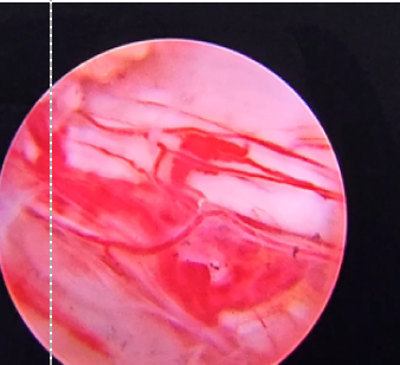

Dr. Khanna is also the recipient of the prestigious AO Spine International Fellowship from the globally renowned Schön Klinik, Munich, Germany, where he received training in advanced Endoscopic and Minimally Invasive Spine Surgery (MIS Spine Surgery).